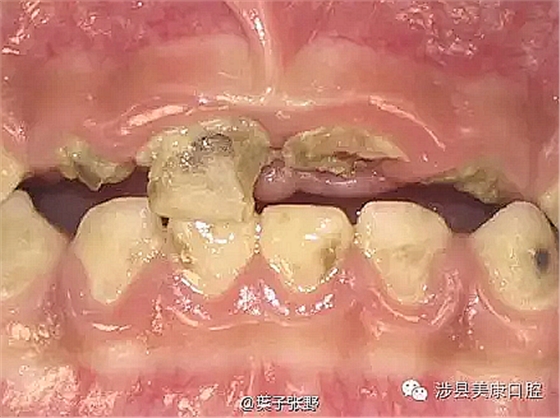

![I6P_R]CQ}]M_KI`I6[5(4_O.png I6P_R]CQ}]M_KI`I6[5(4_O.png](/Mobile/UploadFiles/FCK/2017-04/6362664321377607179638808.png_280.jpg)

影響乳牙下方的恒牙胚。

造成恒牙釉質(zhì)發(fā)育不良。

![%ZE{HJY7[$E@]P[}W0CMW~4.png %ZE{HJY7[$E@]P[}W0CMW~4.png](/Mobile/UploadFiles/FCK/2017-04/6362664370621357178946990.png_280.jpg)

引起恒牙萌出亂位。

引起牙齦發(fā)炎。

引起牙齒錯位。